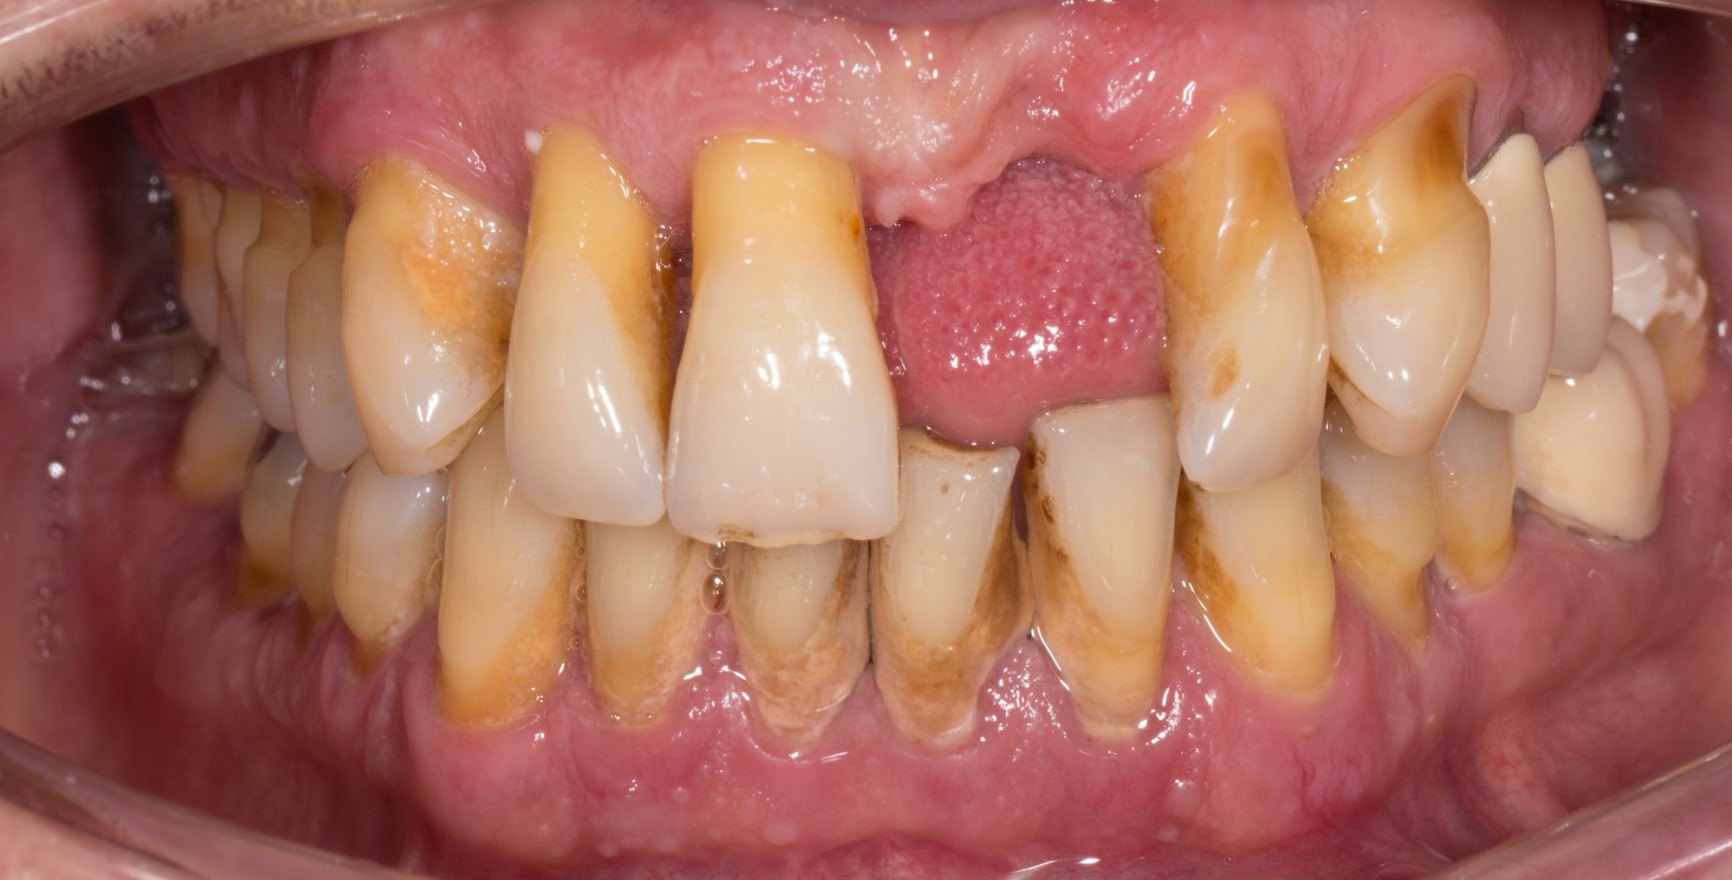

On distingue l'état de santé parodontale clinique d'un parodonte intact de celui d'un parodonte réduit déjà affecté par une perte d'attache clinique. Cette perte d'attache peut se produire :

à la suite d'une l'inflammation au cours d'une parodontite. La santé parodontale clinique décrit alors un état stable après l'achèvement réussi du traitement parodontal.

Le critère clinique est toujours l'absence de saignement lors d'un sondage minutieux (saignement au sondage = BoP). Une distinction est faite entre un diagnostic spécifique au site/à la dent avec un résultat BoP négatif au site de mesure correspondant, et un diagnostic au niveau de la dent ou du patient, pour lequel une valeur seuil d'un BoP ≤ 10 % répond toujours aux critères de santé parodontale clinique. La profondeur de sondage des poches ne doit pas dépasser 3 mm. Dans un parodonte réduit après un traitement parodontal, une valeur seuil de 4 mm est encore considérée comme un état stable (Matuliene et al., 2008).